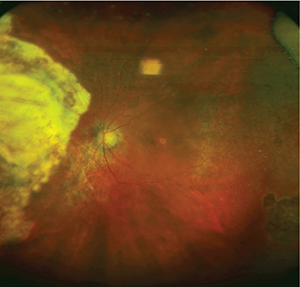

![]() | Figure 2. This 62-year-old woman also required full-thickness retino-choroidal biopsy (FTRCB). She presented with subacute vision loss and was found to have active creamy yellow/white infiltrates in the nasal/inferior midperiphery (A). On optical coherence tomography (B), the finding appeared to be largely confined to the subretinal space and to be less impressive than the previous case. She had rapidly progressive vision loss in both eyes over a few weeks and an entirely negative workup, which prompted the FTRCB. |

• Beware the unavoidable. Consider specific intraoperative challenges before surgery. Remember that in these cases, the eye is usually injected, the conjunctiva bleeds a lot, posterior synechiae may be present and media opacity issues may arise—all of which you should account for in your planning (Figure 2).